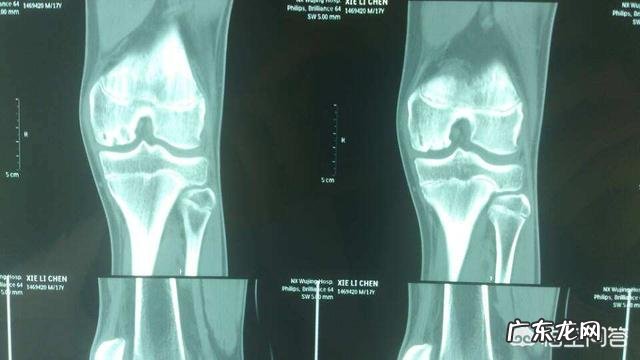

困扰现在老年人生活质量,有一个大的问题就是膝关节痛,有的医院现在很草率,去医院拍个X线,看到关节间隙变窄,就建议患者做关节置换,这就是在扯淡,真心是一种过度医疗,有不少人不必做这个手术的 。

在青岛遇到一个阿姨,60多岁,走路膝关节疼痛,去医院拍了一个X光片,核磁都没做,医生沟通几分钟,直接建议膝关节置换,一个膝关节手术费用20万,也正是如此昂贵的费用,存在较高的利润空间,不是熟人,差不多符合就建议做!